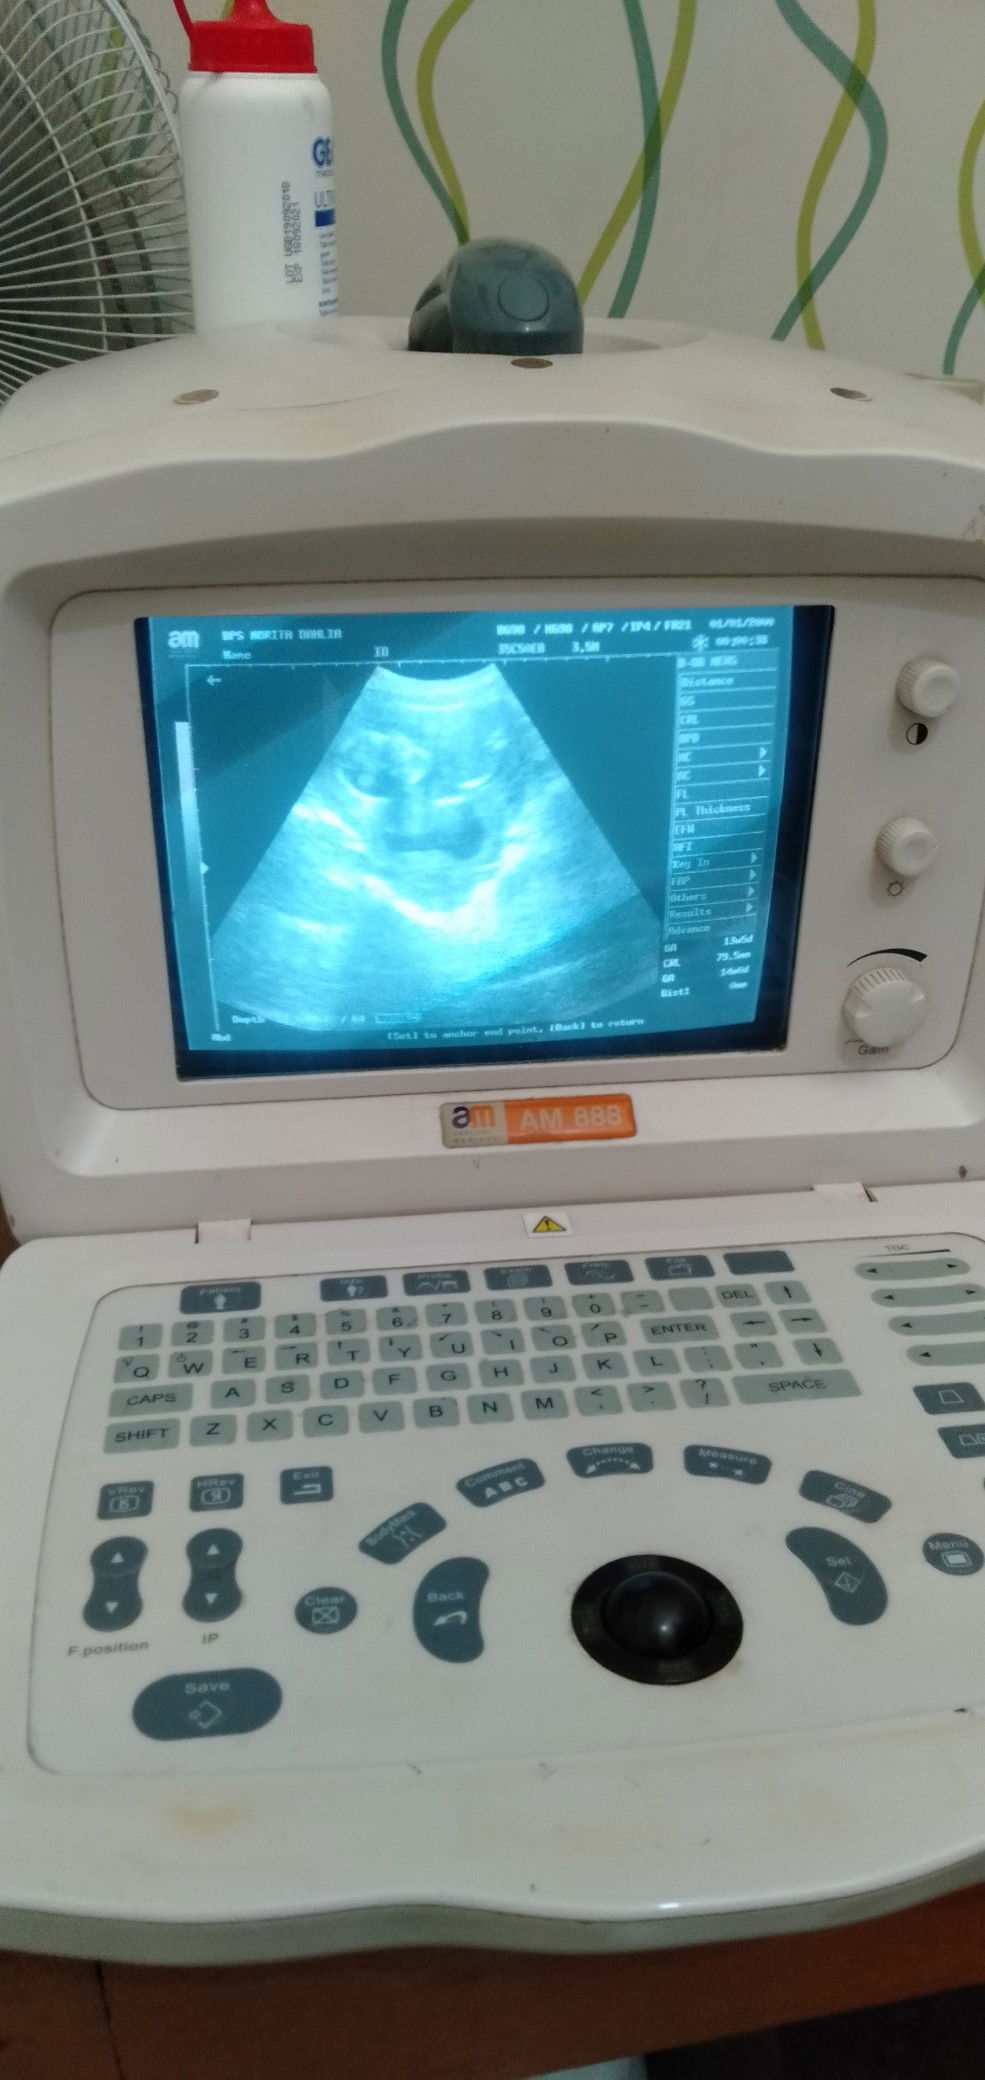

ini kembar atau gk sih bund:)

Dokternya ga bilang bun?

gk bilang apaΒ² bun